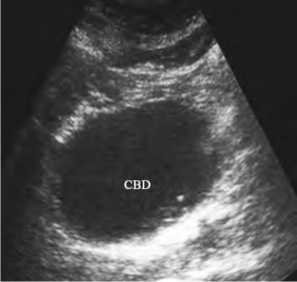

1.先天性胆总管囊肿超声表现 超声表现为肝总管、胆总管的囊性扩张,显示为右上腹部椭圆形或梭形的液性暗区(图25-18),位于胆囊颈内后方、门静脉前方,其长径与胆总管的走向一致。液性暗区内部清晰,后回声增强。

图25-18 先天性胆总管囊肿声像图